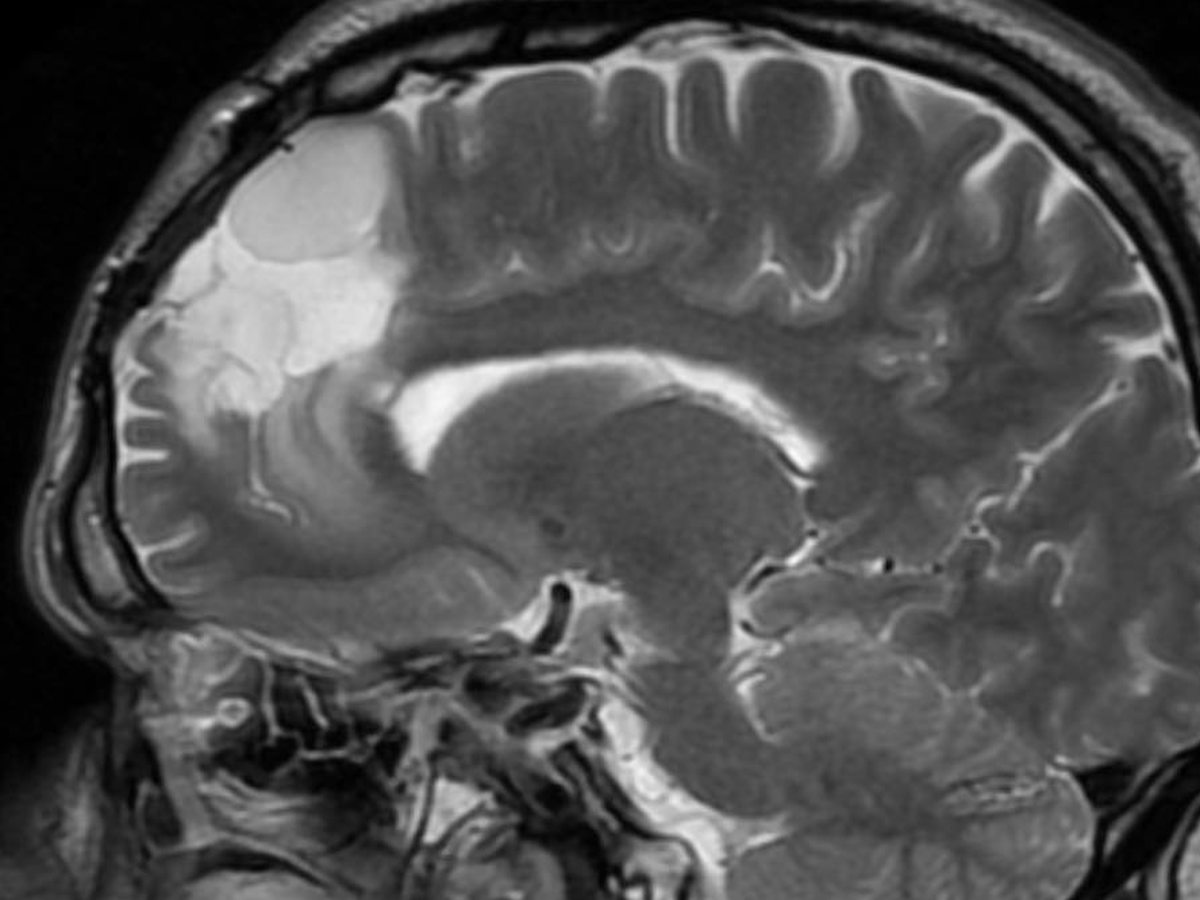

-Derek currently has two potentially deadly infections in his spinal cord, along with IDH Mutant or Astrocytoma, which is a brain cancer that there is currently no cure for. On top of all of this, he has developed 3 masses on and in his liver. With his current regimen of over 20 pills a day, driving to Lexington for appointments 6-8x a week and to Vanderbilt often, as well being a Dad and continuing his duties there, the financial burden has been significant. He has been fighting disability which feels like a losing battle for 2 years. -

Derek has been facing an ongoing battle with brain cancer and other medical issues. Most recently, he learned that he has a severe infection on his spinal cord, a cancerous tumor in his brain, as well as his liver. He has had to have a PICC line put in, and will be down for at least 8-10 weeks, if not longer. Insurance is being a pain and not wanting to cover many parts of his treatment, including home health, which is causing him to have to stay in the hospital, and miss valuable time with his son and best friend, Jayden.